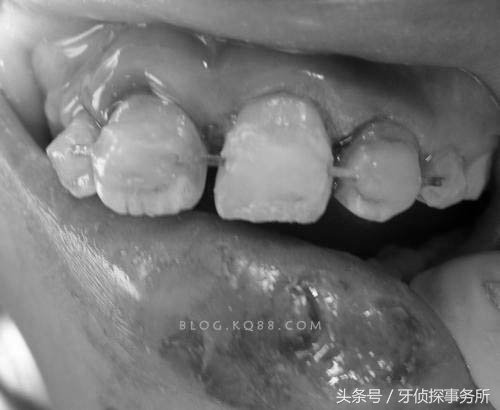

1、部分脱位

碰撞后乳牙在外力的作用下向外或向内倾斜移位后部分脱出牙槽窝时,可将外伤牙恢复到原位后结扎固定,一般预后较好,但日后有可能发生牙髓坏死,根尖感染或牙槽脓肿。如果接近替牙期或者乳牙牙根已吸收1/2以上者可以考虑拔除该颗松动乳牙。